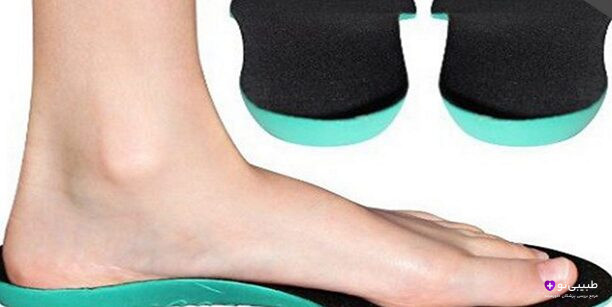

استفاده از کفش مناسب و ارتز

برای درمان درد پاشنه پا باید از کفشهایی که پشتیبانی خوبی روی مچ دارند استفاده کرد. همچنین اندازه کفش باید کاملا مناسب و استاندارد باشد. اکیدا توصیه میشود در صورت ابتلا به درد پاشنه پا از پوشیدن کفشهای تنگ خودداری کنید.

کفشهای پاشنه بلند نیز فشار بیشتری روی عضلات ساق پا و پاشنه وارد میکنند. استفاده از ارتز به دلیل کمک به ساختار اندامهای مختلف پا و کاهش درد پاشنه توصیه میگردد. ارتزها لوازم پزشکی به شمار میروند که شامل انواع مختلفی نظیر:

- بریس

- کفی طبی

- کفش طبی

- اسپلینت

هستند.